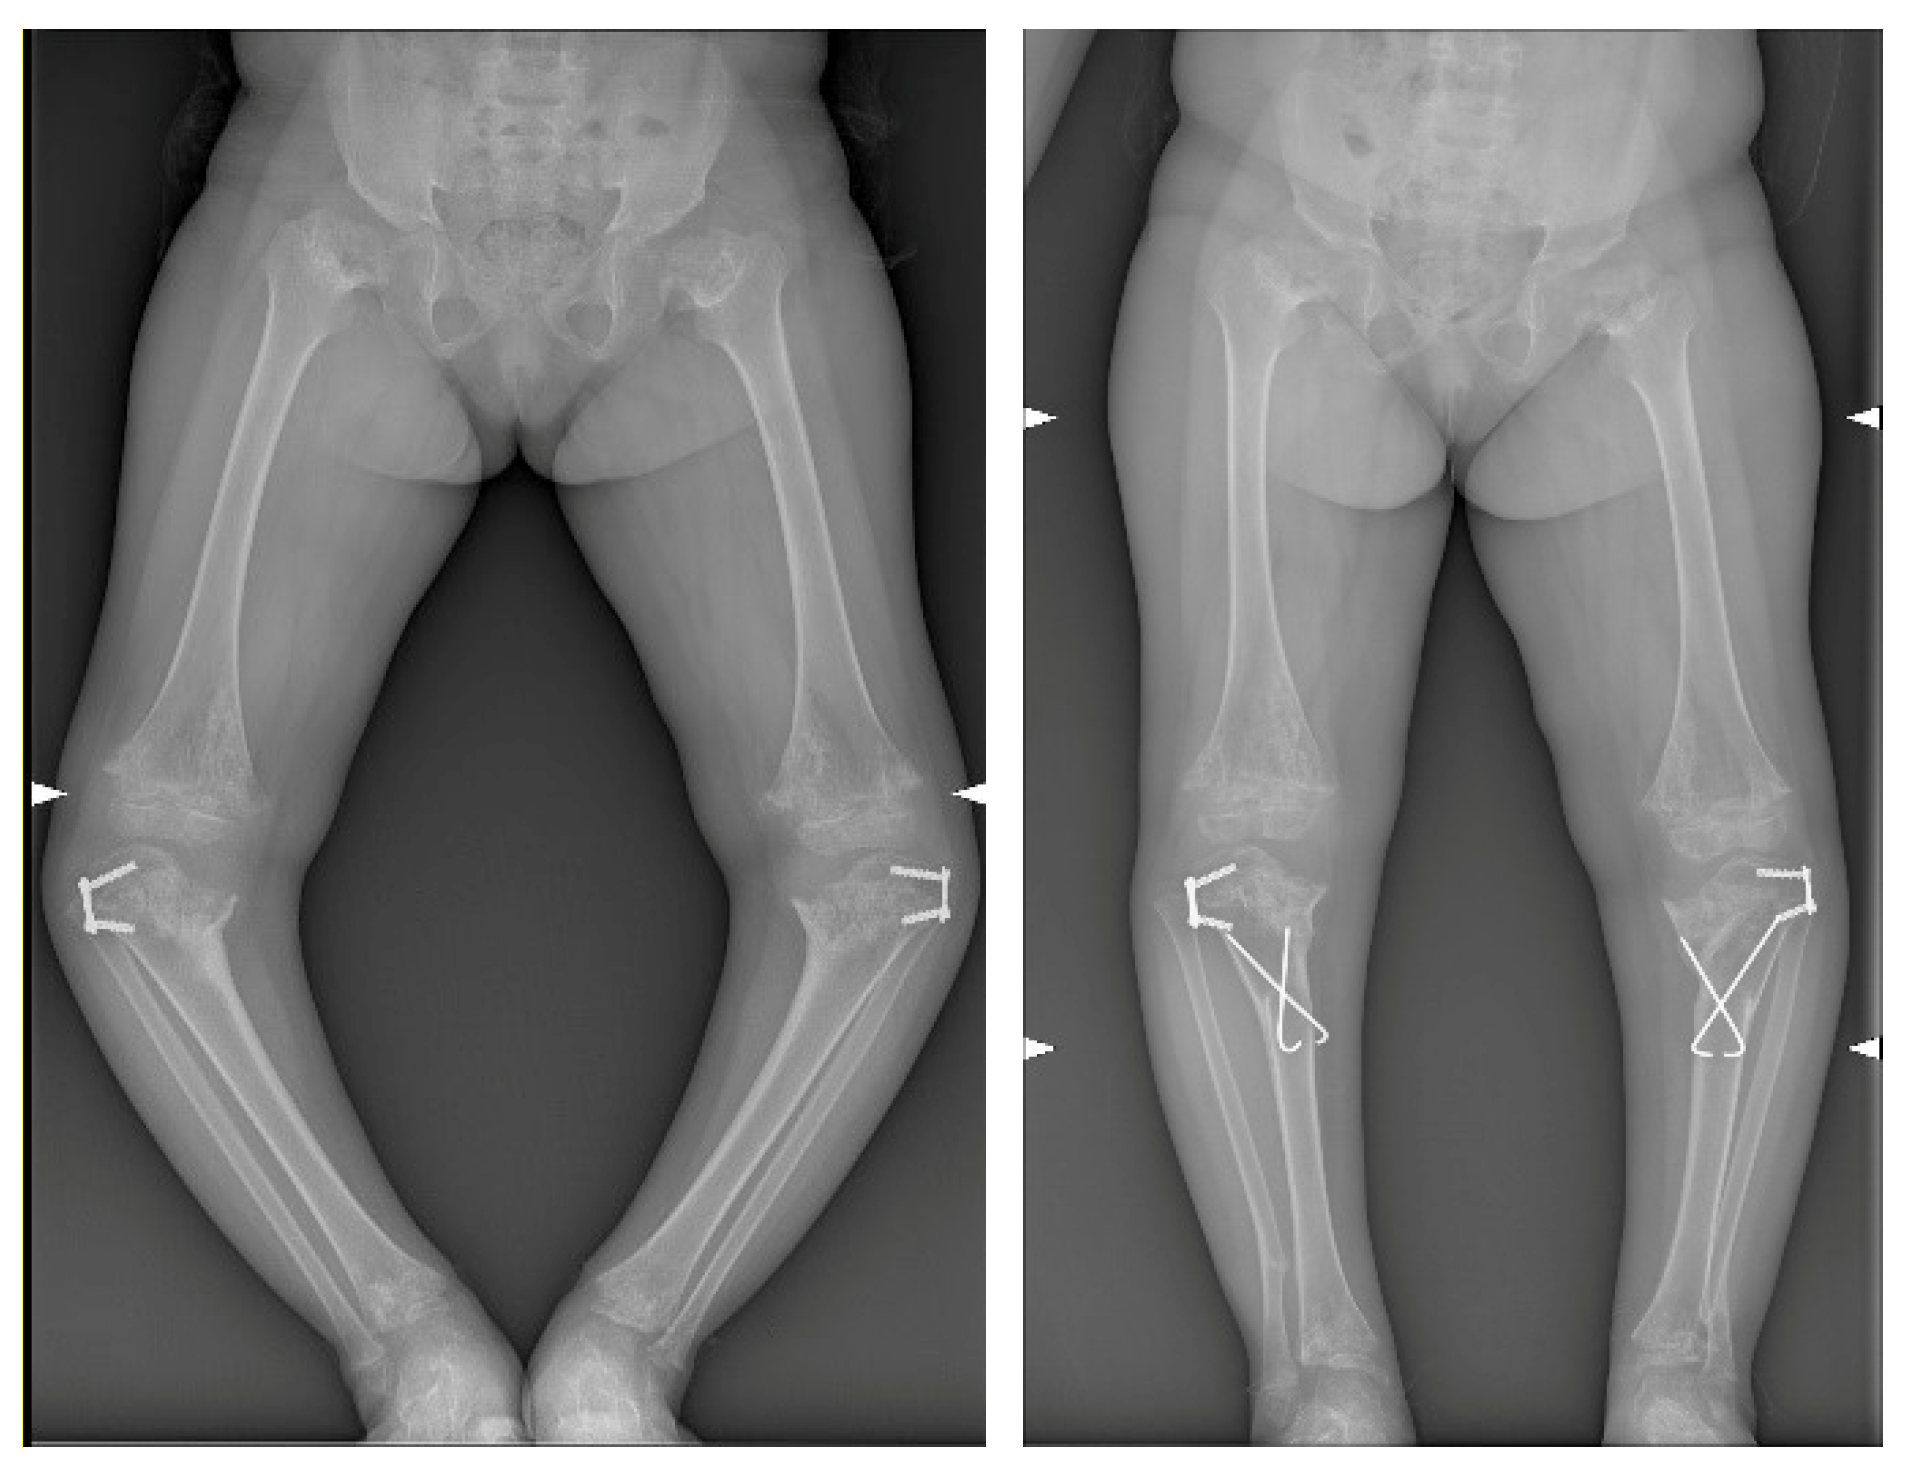

3. Results

| MAD | aTFA | FC-TS Angle | ||||

|---|---|---|---|---|---|---|

| preop | postop | preop | postop | preop | postop | |

| right | −100 mm | −39 mm | −45° | −3° | 49° | 86° |

| left | −100 mm | −51 mm | −44° | −15° | 55° | 72° |